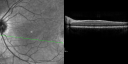

OD: Vertical C/D ratio is 0.2. There is no posterior vitreous separation and 2+ multiple macular drusen. There is no bull’s-eye maculopathy.

OS: Vertical C/D ratio is 0.2. There is no posterior vitreous separation, again there are 2+ multifocal small cuticular macular drusen.

OCT SCAN: The OCT scans were normal. Photos confirm clinical findings.

FLUORESCEIN ANGIOGRAPHY: Fluorescein angiography shows early hyperfluorescence of tiny macular drusen scattered throughout the macula in both eyes.